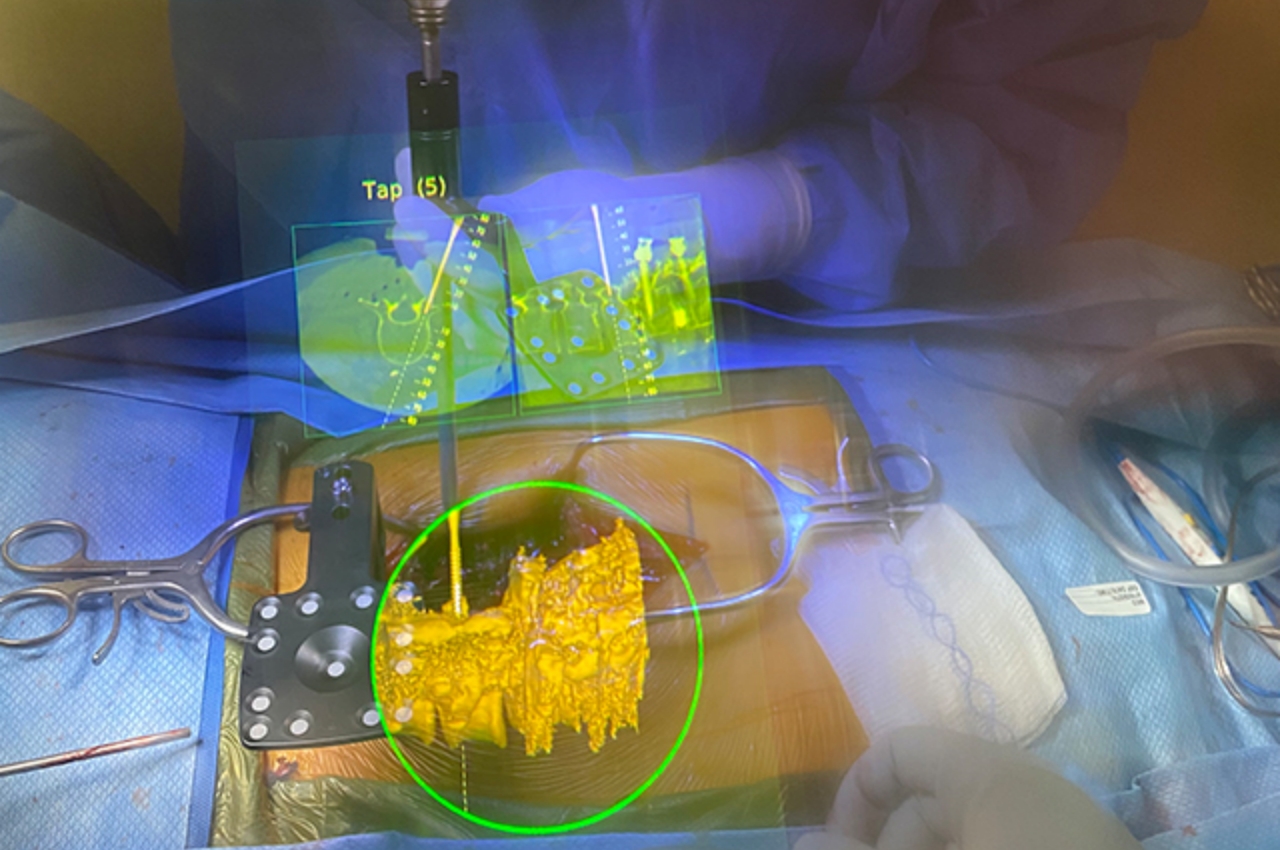

Chirurgia AR

Grazie a Hollywood, molte persone probabilmente immaginano che la chirurgia nel mondo dell'AR e del Metaverso coinvolga medici che eseguono procedure a miglia o addirittura paesi di distanza dal paziente. Anche se ciò potrebbe avere vantaggi salvavita, non abbiamo ancora bisogno di andare così lontano per raccogliere i vantaggi della tecnologia in sala operatoria. Essere semplicemente in grado di vedere più informazioni di quelle che abbiamo fisicamente di fronte fa molto per migliorare la nostra conoscenza e comprensione, che è davvero il cuore della realtà aumentata, senza clamore e sensazionalismo.

I medici richiedono molta immaginazione quando lavorano sui pazienti e non nel modo in cui voli di fantasia. Potrebbero non avere una visione chiara di ciò su cui stanno operando o devono lavorare con materiali microscopici che sarebbero impossibili da vedere ad occhio nudo. Sebbene questi professionisti lavorino in questo modo da decenni, ciò non significa che le cose debbano rimanere così, soprattutto se la tecnologia può aiutare ad alleggerire il carico.

Gli interventi chirurgici assistiti da AR sono già stati eseguiti con molto successo, ma spesso non si sente parlare di quelli in contrasto con le notizie su questa o quella nuova piattaforma Metaverse. Essere in grado di vedere dove perforare un osso o dove mettere una vite può rendere le procedure più rapide e sicure. Ovviamente, avrai bisogno di occhiali AR migliori per farlo accadere perché gli attuali modelli di consumo che abbiamo semplicemente non lo taglieranno sul tavolo operatorio, gioco di parole.

Progettista: Augmedics (via Medicina John Hopkins )